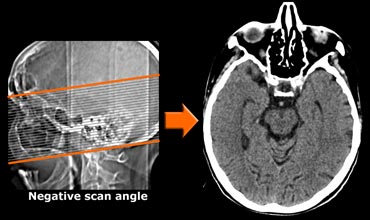

CT with negative scan angle for optimal vizualisation of the hippocampus in the transverse plane CT with negative scan angle for optimal vizualisation of the hippocampus in the transverse plane

CT protocol

CT can be useful when contraindications prevent MRI or when the only reason for imaging is to rule out surgically treatable causes of cognitive decline.

In the transverse plane the scan angle should be parallel to the long axis of the temporal lobe.

Use of multi-detector CT will enable coronally reformatted images to be reconstructed perpendicular to the long axis of the temporal lobe for optimal vizualisation of the hippocampus.

Spiral CT of the brain with coronal reconstructions. Spiral CT of the brain with coronal reconstructions.